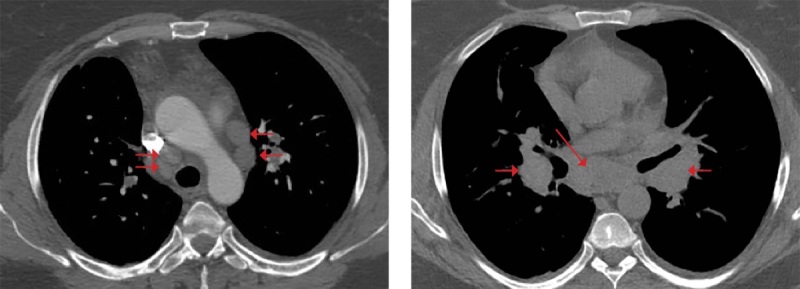

库欣病是一种罕见的严重神经内分泌疾病,由垂体肿瘤长期过度分泌促肾上腺皮质激素引起。内源性高皮质醇症患者体内皮质醇的生理浓度过高,具有类似于全身糖皮质激素治疗的免疫抑制和抗炎作用。这可能会降低患者并发的自身免疫性炎症疾病的活性。另一方面,在治疗库欣病的过程中,皮质醇水平的降低可能与免疫系统的重新激活有关,从而带来自身免疫性疾病发病或复发的风险。我们介绍了自己的一个临床病例,该病例显示,在对库欣病进行手术治疗后,出现了肉样瘤病。

Cushing's disease is a rare severe neuroendocrine disorder caused by chronic overproduction of adrenocorticotropic hormone by a pituitary tumor. Supraphysiological concentrations of cortisol in endogenous hypercortisolism have an immunosuppressive and anti-inflammatory effect similar to therapy with systemic glucocorticosteroids. This may reduce the activity of the patient's concomitant autoimmune inflammatory diseases. On the other hand, a decrease in cortisol levels during treatment for Cushing's disease may be associated with a reactivation of the immune system that pose a risk of onset or recurrence of an autoimmune disorder. We present our own clinical case demonstrating the development of sarcoidosis after surgical treatment of Cushing's disease.